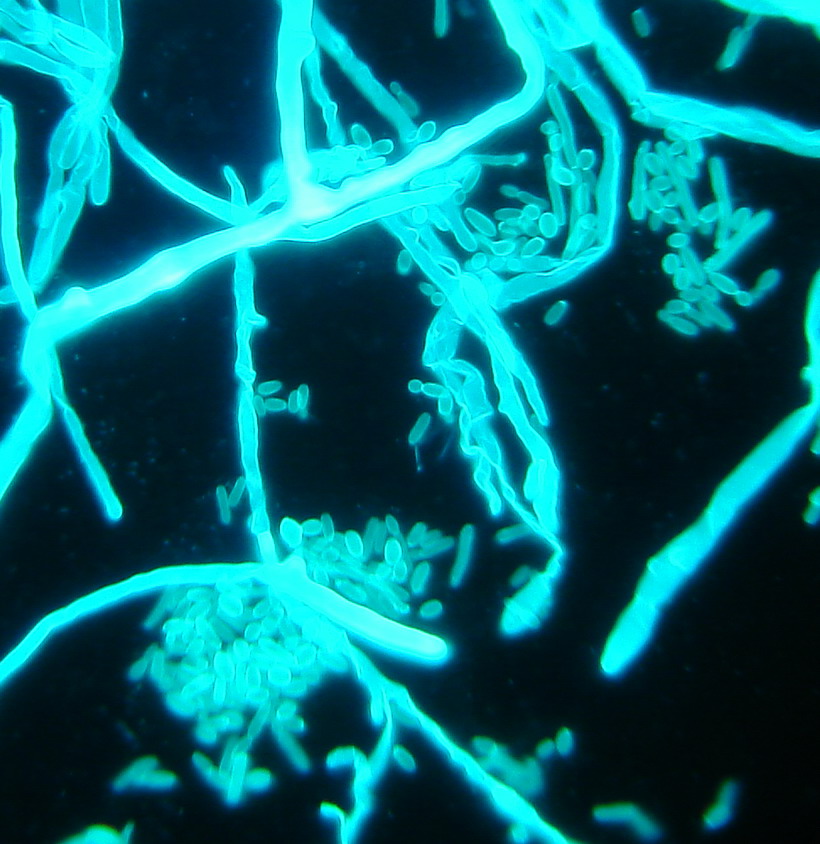

Christian Doppler Laboratory for Invasive Fungal Infections

In 2015, a “Christian Doppler Laboratory for Invasive Fungal Infections” was set up. Within the estimated 2 million fungal species on earth, around 600 cause diseases in humans. The most significant are Candida, Aspergillus, Mucorales and Cryptococcus. Fungal infections are increasing and they are associated with excessive morbidity and mortality (Fig. 3). Over 300 million people are acutely or chronically infected, with the results of death, long term illness and reduced work capacity. The reasons for emergence are probably multifactorial, e.g. the advent of medical progress, the successful application of immunosuppression in transplant patients and the use of immunomodulatory agents to treat various diseases from cancer to rheumatoid arthritis.

A disturbing and rapid increase in infections caused by antimycotic-resistant fungal pathogens is one major public health concern facing medicine today. Most severe and fatal cases result from healthcare-associated fungal infections, which are increasingly caused by Candida, Aspergillus and Mucorales. Hence, one significant focus is the investigation of azole and echinocandin resistance in yeasts and moulds and the discovery of new resistance mechanisms. Another major focus is on identifying the underlying mode of amphotericin B resistance in Aspergillus terreus. In this context, we are evaluating mitochondria as crucial modulators of polyene resistance. The mission of HMM is to bridge the translational gap between basic research and the development of novel antifungal drugs. HMM will support epidemiologic, translational and clinical studies to improve the management of fungal diseases.